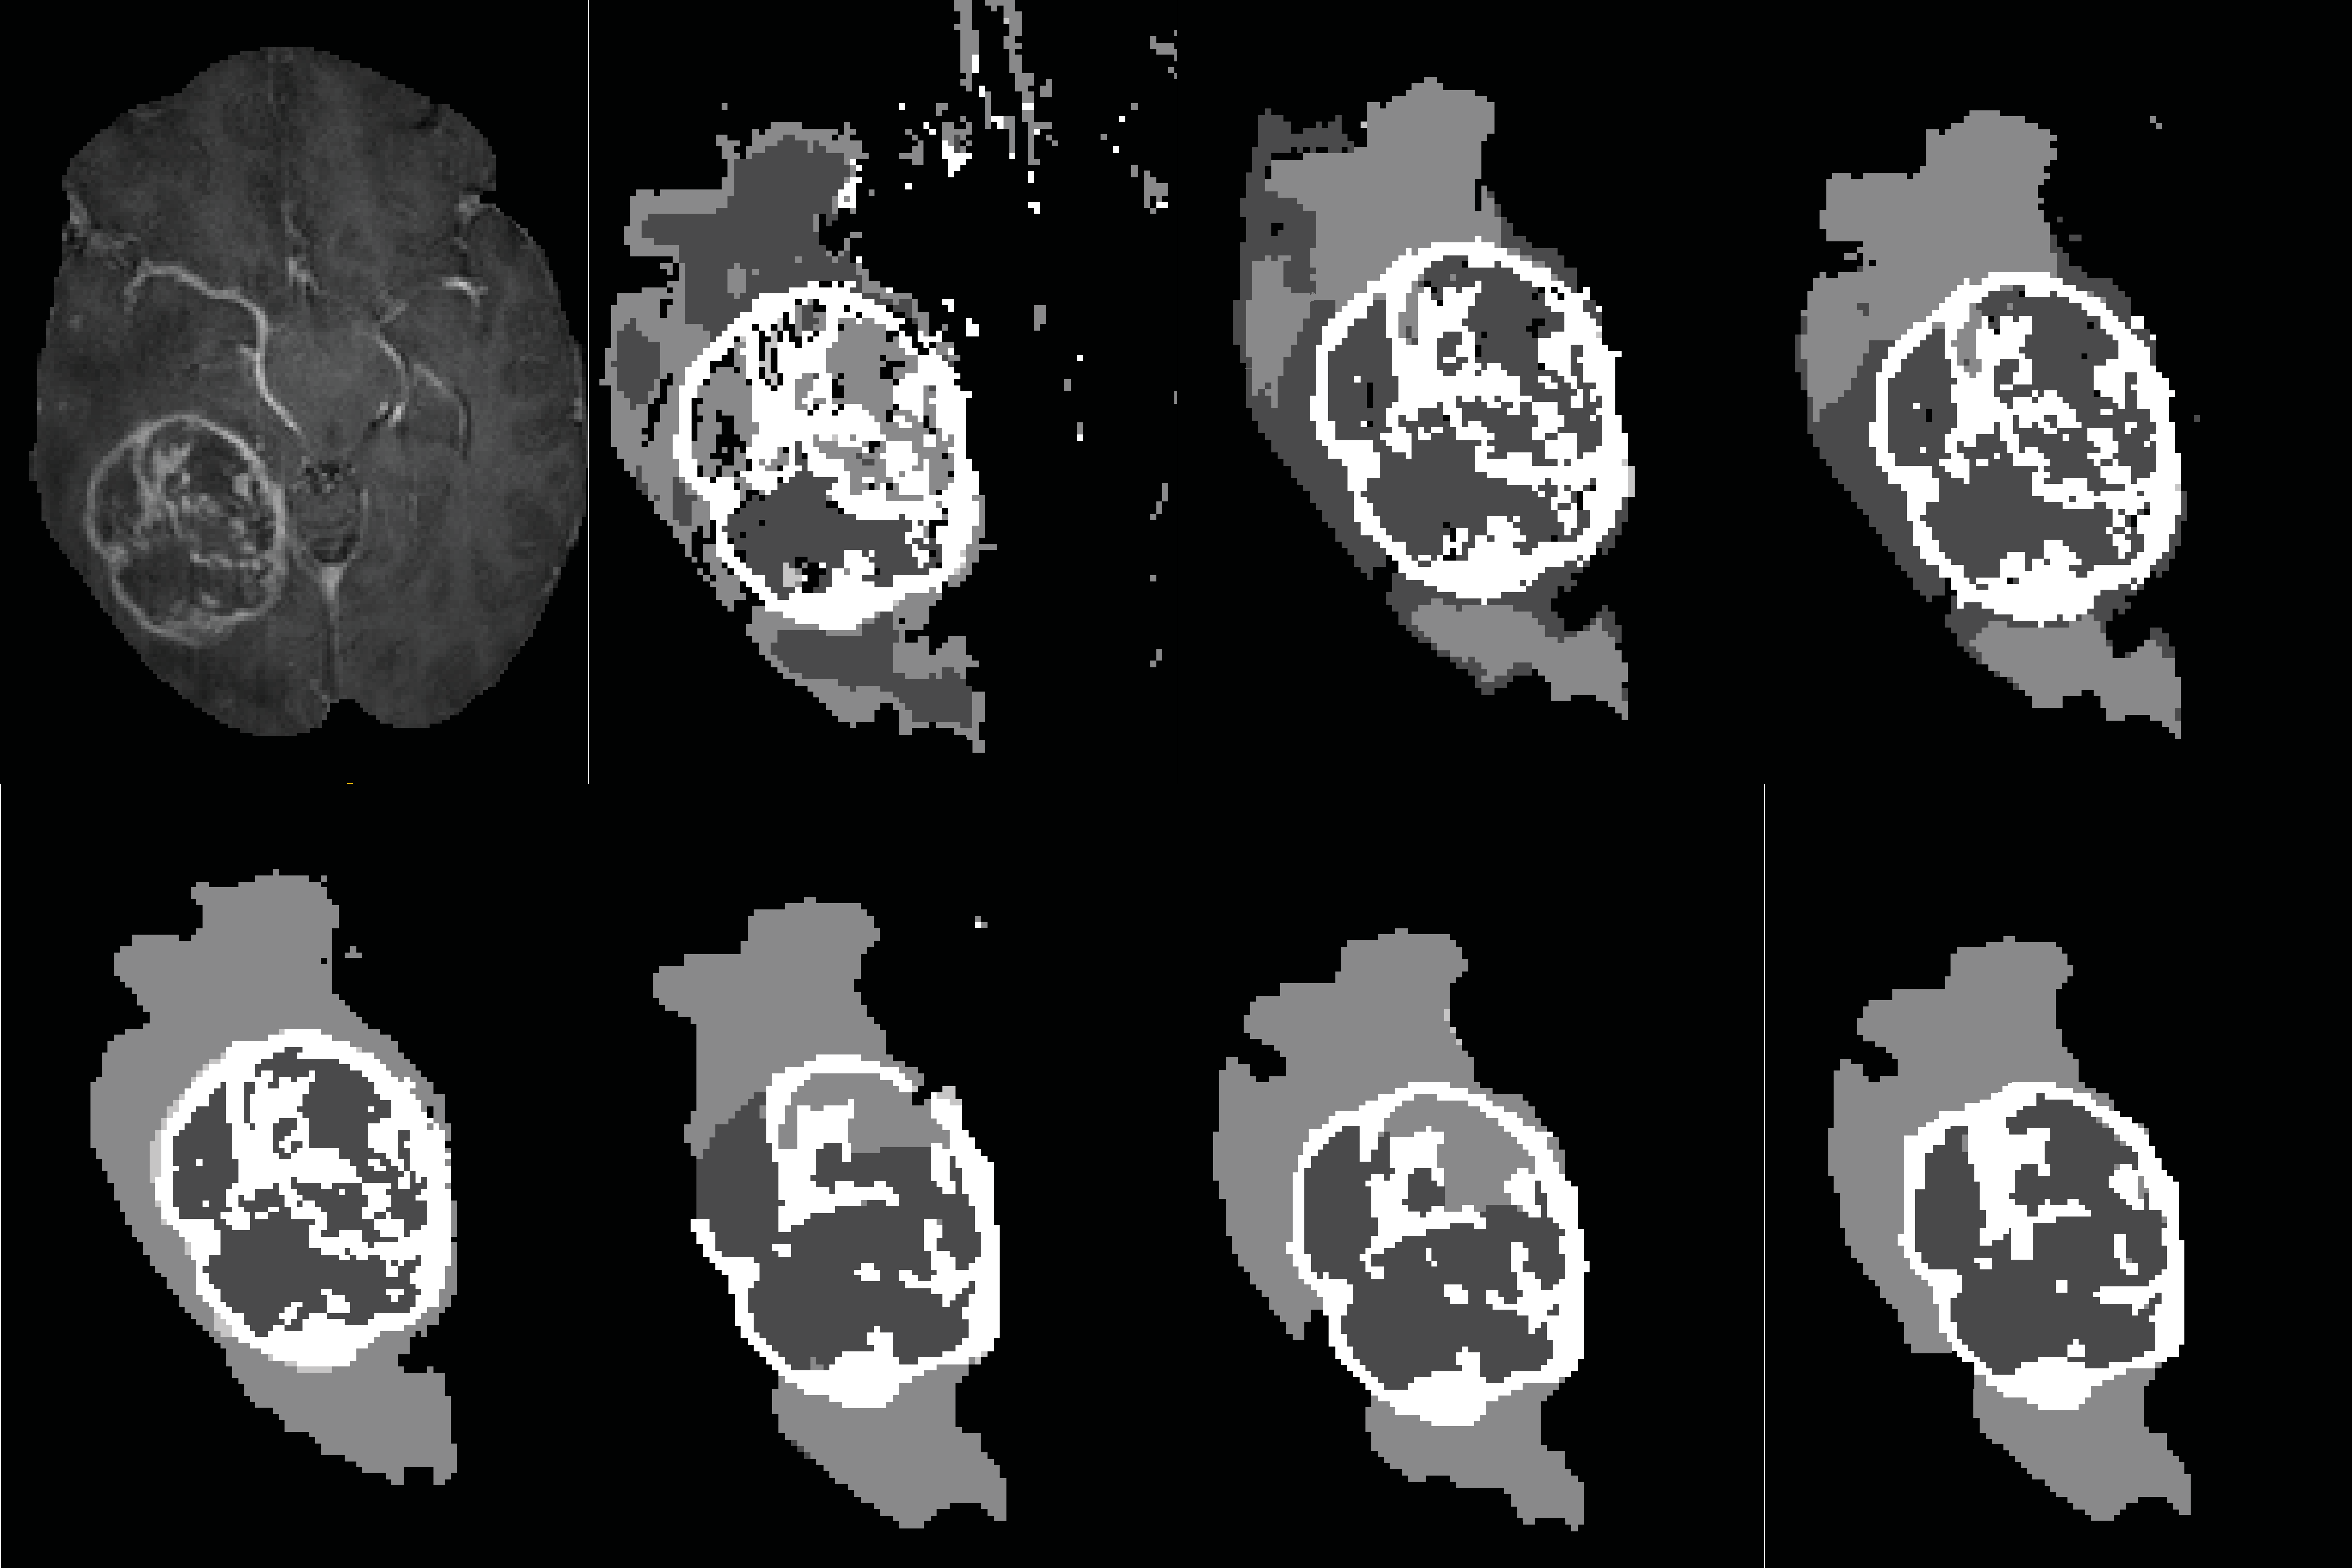

Figure 5: Illustration of brain tumor segmentation maps predicted by different variations of SVM. Top row from left to right : T1C modality, KSVM, KSVM*, PKSVM*. Bottom row from left to right: ground truth, KSVM-CRF, KSVM*-CRF, PKSVM*-CRF.

Figure 5 shows a visualisation of segmentation results, for different variations of our SVM method. This illustrates the contribution of adding spatial features, using a CRF and using our improved kernel function, in improving the general performance of the SVM approach.